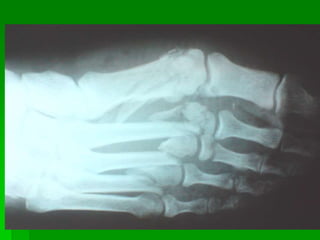

Lesión ósea

Lesiones de pie

Cuerpo insertado

Base de los

metatarsianos

Huesos

cuneiformes

Escafoides

Cabeza del

astrágalo

Cuboides

Calcáneo